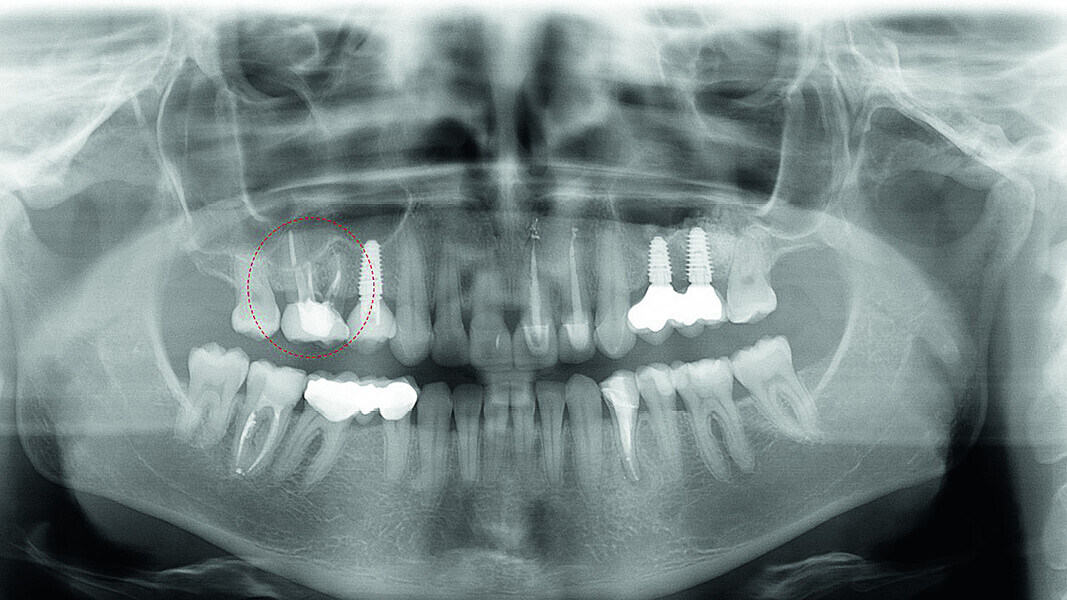

Digital workflow and application of PRF and ozone therapy in oral rehabilitation